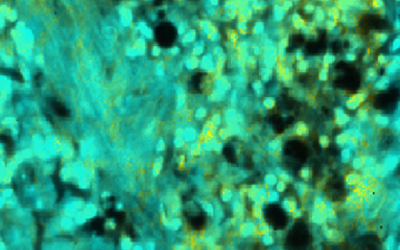

UCLA Bioengineer Advances Ultrafast, High-Res Microscopic Imaging Technique Using Fluorescence

Liang Gao, an assistant professor of bioengineering at the UCLA Samueli School of Engineering, and his colleagues have developed the world’s fastest fluorescence lifetime imaging microscopy (FLIM) technology.